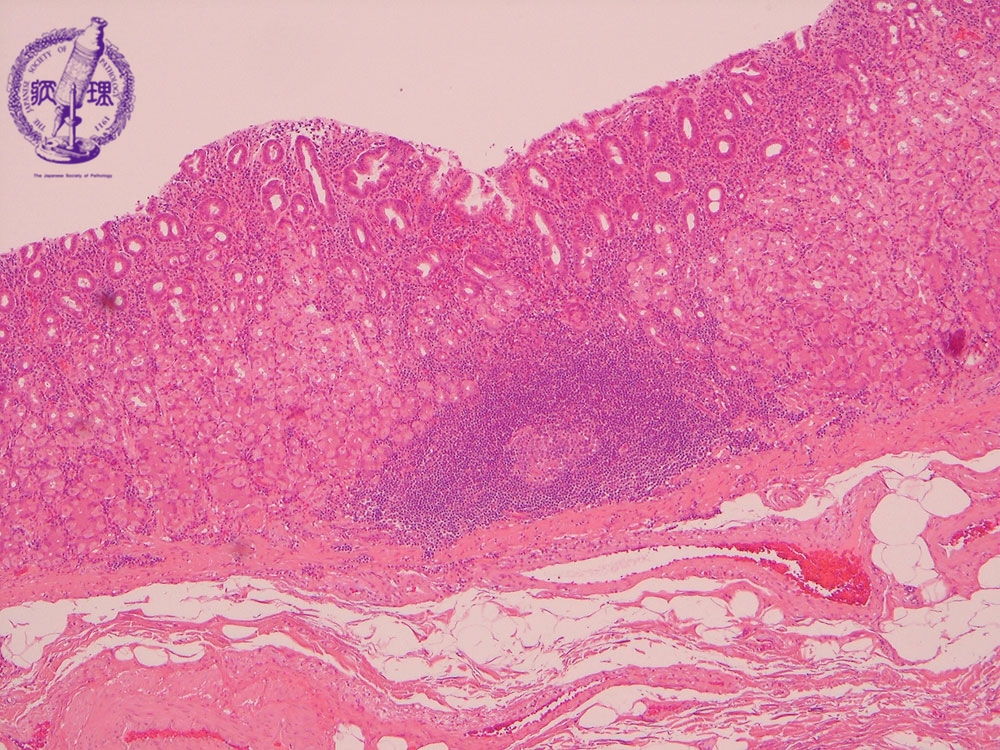

Microscopic view (H&E stain, low power): Chronic gastritis. There is chronic inflammation of the gastric cardia, predominantly at the mucosal surface. Lymphoid follicles form within fundic glands (circle), accompanied by glandular destruction.